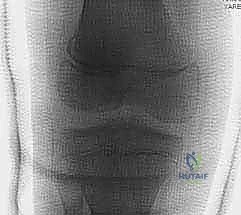

كسور صفيحة النمو الفخذية البعيدة عند الأطفال: دليل شامل للعلاج مع الأستاذ الدكتور محمد هطيف في صنعاء

تعرف على كسور صفيحة النمو الفخذية البعيدة لدى الأطفال، أسبابها، تشخيصها، وخيارات العلاج المتقدمة على يد الأستاذ الدكتور محمد هطيف، خبير جرا…